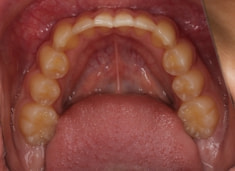

治療前